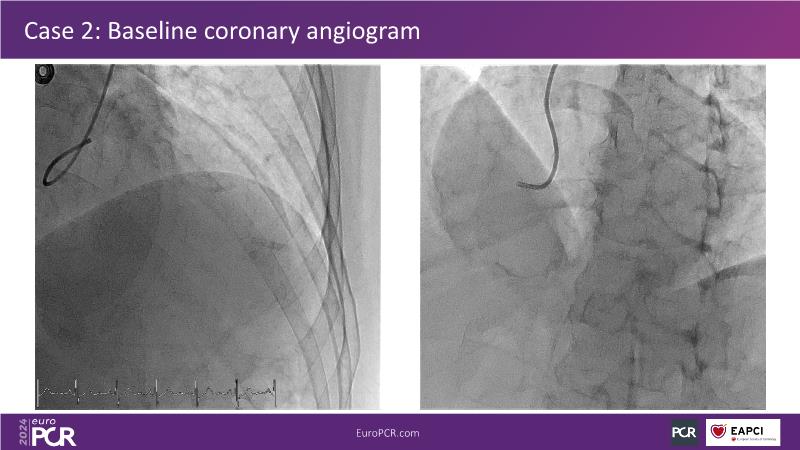

Watch this session on PCI in diabetic patients to learn about a groundbreaking technology addressing the complexities of this critical subgroup. Discover the next-generation DES and DCB stent platform and the innovative Envisolution technology behind it. Understand how it works, its advantages in managing complex cases, and what sets it apart from other technologies. Gain insights into the future of polymer-free DES + DCB stent technology and its potential impact on patient care.